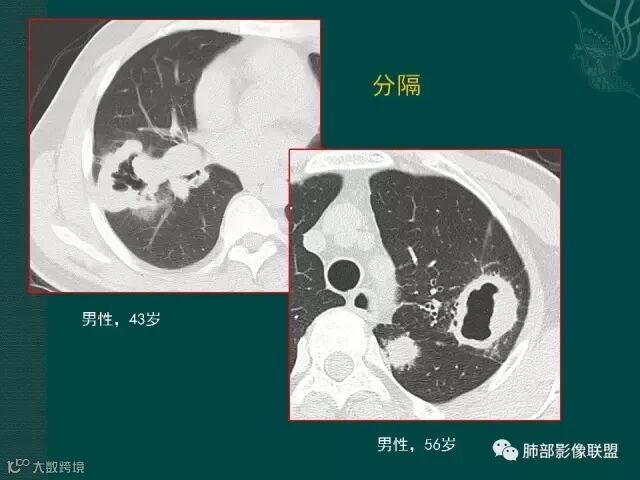

上一个是磨玻璃密度肺癌,边缘清晰,内有分隔,空洞型肺癌伴磨玻璃密度影的,100%为腺癌,很显然这是个假性空洞;

下一个也是肺癌,内有分隔,外下缘箭头所示也是磨玻璃影,这也是腺癌,同时可见叶间裂有转移灶。